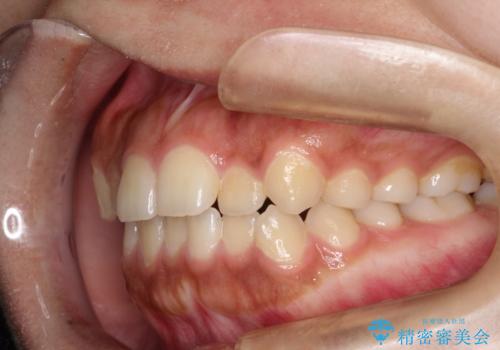

インビザライン 前歯のがたつきを目立たず矯正

- 前歯のがたつきが気になるとのことで来院されました。

インビザラインにて治療を行いました。

わずかに歯と歯の間に隙間を作り、歯列矯正を行いました。

マウスピースをしっかりと使用していただけたので、スムーズに治療を終了することができました。